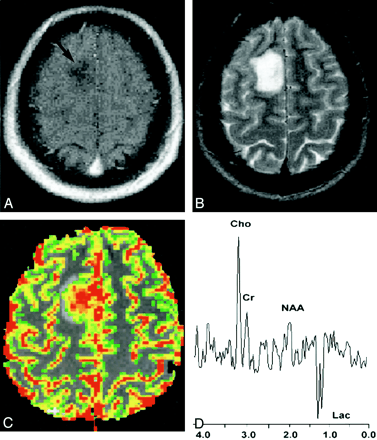

图1:20岁女性,经活检证实为高级神经胶质瘤。

A对比度增强的轴向T1加权图像(600/14/1 [TR / TE / NEX] )在右额叶区域显示出模糊不清的非增强块(箭头)。常规MR图像缺乏增强提示低级神经胶质瘤。

B,轴向T2加权图像(3400/119/1)显示肿块中信号强度增加,肿瘤周围水肿较小。由于缺乏增强,较小水肿,无坏死和无肿块效应,该肿块在常规MR成像中被定为低度胶质瘤。

C,具有rCBV彩色叠加图的梯度回波(1000/54)轴向灌注MR图像显示,随着高等级胶质瘤,rCBV为7.72的灌注增加。

D,来自质子MR光谱的PRESS序列(1500/144)光谱显示,Cho / NAA比为2.60时,Cho显着升高,NAA显着降低,并且乳酸(Lac)升高,与高级别神经胶质瘤一致。